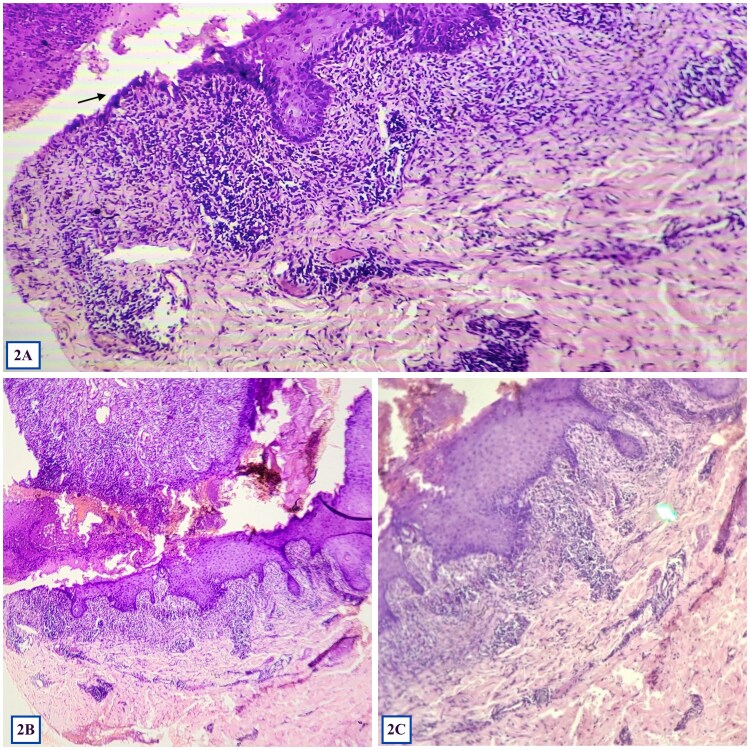

67岁女性2型糖尿病患者表现为顽固性疼痛口腔糜烂和胸部紫色病变,口服皮质类固醇反应最小。由于既往食欲下降、体重减轻且治疗效果不佳,进一步评估发现c反应肽、desmoglin -3抗体、碳水化合物抗原19-9升高,腹膜内分叶状均匀增强的淋巴结肿块,后者提示淋巴瘤。口腔黏膜组织病理学提示副肿瘤性天疱疮。患者转至肿瘤科接受进一步治疗。该病例强调了对具有非典型组织病理学的顽固性皮肤粘膜病变的老年患者进行彻底评估的重要性。

A 67-year-old female with type-2 diabetes mellitus presented with recalcitrant painful oral erosions and violaceous chest lesions, that responded minimally to oral corticosteroids. Due to history of decreased appetite, weight loss and poor therapeutic response, further evaluation was performed, revealing elevated C-Reactive Peptide, Desmoglein-3 antibody, Carbohydrate Antigen 19-9, and intraperitoneal lobulated homogeneously enhancing nodal mass, the latter indicating lymphoma. Histopathology from oral mucosa was suggestive of paraneoplastic pemphigus. The patient was referred to oncology department for further management. This case underscores the importance of thorough evaluation in elderly patients with recalcitrant mucocutaneous lesions with atypical histopathology.